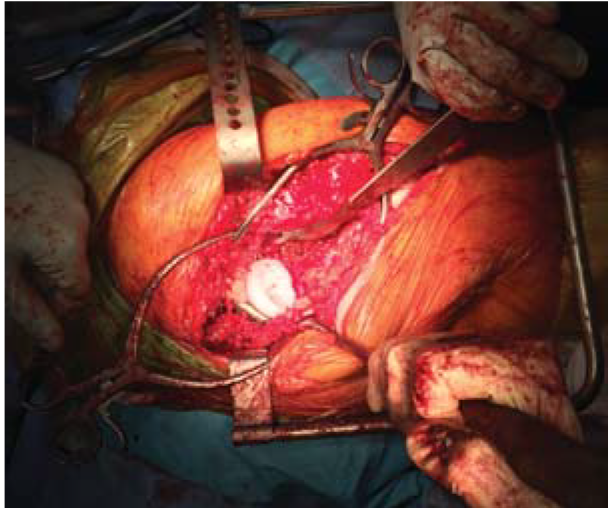

进行手术,放入假体

医生对恶性肿瘤患者进行手术,植入带 Ha涂层+抗感染银离子的无菌钛合金植入体。

手术成功